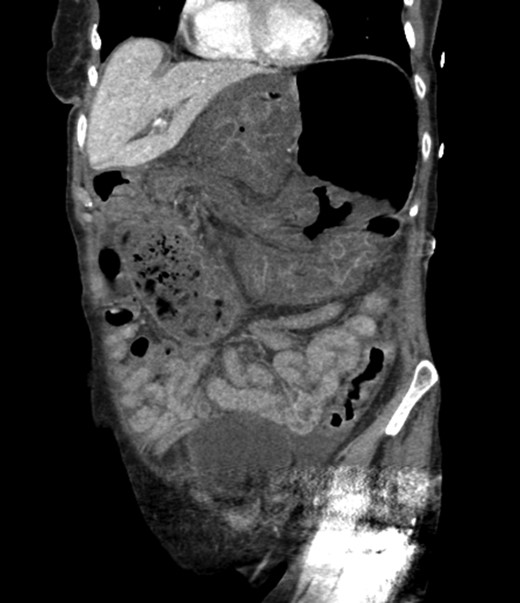

An 81-year-old female with a medical history of CAD with stents, hyperlipidemia, hypothyroidism, GERD, recent UTI, pancreatic cyst, constipation, anemia and leukopenia presented to the ED with a 1 day history of mild, diffuse and cramping abdominal pain. The patient was unable to give an accurate history, but the son at bedside supplemented this reporting that for several years the patient had been experiencing ill-defined abdominal discomfort. Physical exam showed a soft abdomen with mild tenderness and no evidence of peritonitis. A CT scan of the abdomen and pelvis with IV and PO contrast (Fig. 1) showed edematous changes to the mesentery of the small and large bowel with swirling of vessels indicative of internal hernia. The stomach was also noted to be distended with both air and fluid as a consequence of posterior compression by the hernia contents (Fig. 2). A surgical consult was obtained, a nasogastric tube and Foley catheter were placed, antibiotics were started, and the patient was taken for an exploratory laparotomy. Upon entering the abdomen through a vertical midline incision, 1.5 l of ascites was drained revealing a diffusely edematous mesentery. A large portion of the small bowel was seen to be herniated through the Foramen of Winslow (Fig. 3). A Kocher maneuver and division of the gastrocolic ligament were then performed to allow release of the herniated small bowel. It was at this time that, in addition to small bowel, a large portion of the ascending and transverse colon was noted to be herniated through the foramen of Winslow. The small bowel was also seen to be torsed about its own mesentery. Normal anatomy was restored and the bowel noted to be healthy and viable with peristalsis (Fig. 4). Due to the large size of the foramen after reduction and enlargement, it was deemed best to leave it open to prevent any further incarceration or strangulation. The abdomen was closed and the patient tolerated the procedure well. At a follow-up visit 2 months later, the patient had well-healed incisions, was doing well, tolerating a diet, and gaining weight appropriately.

Loops of bowel between IVC, liver, and lesser curvature of the stomach. Arrow small bowel. Arrow head stomach.

Diagnosing an internal hernia is frequently accomplished using physical exam and CT imaging. Abdominal X-ray does have some nonspecific findings suggestive of internal hernia but is usually inadequate for diagnosis. Diagnosis of a foramen of Winslow hernia, however, is only accomplished in 10% of patients preoperatively [3]. As previously mentioned this diagnosis is rare and often presents with vague obstructive type symptoms. This likely contributes to the low occurrence of accurate preoperative diagnosis. However, several radiographic findings were seen in this patient that suggested a foramen of Winslow hernia preoperatively. First, there is visible swirling of the mesentery on the CT scan that is indicative of internal hernia (Fig. 1). Second, there are loops of small bowel that can be visualized between the IVC and the edge of the liver in a supra renal position along the lesser curvature of the stomach (Figs 1 and 2). When compared to a CT of the abdomen and pelvis obtained 4 years prior to presentation, there is actually evidence that this patient had a non-obstructing foramen of Winslow hernia at that time as demonstrated by bowel being visualized in the lesser sack (Fig. 5). These findings, especially small bowel along the lesser curvature of the stomach, are inconsistent with normal anatomy and strongly indicative a foramen of Winslow hernia.